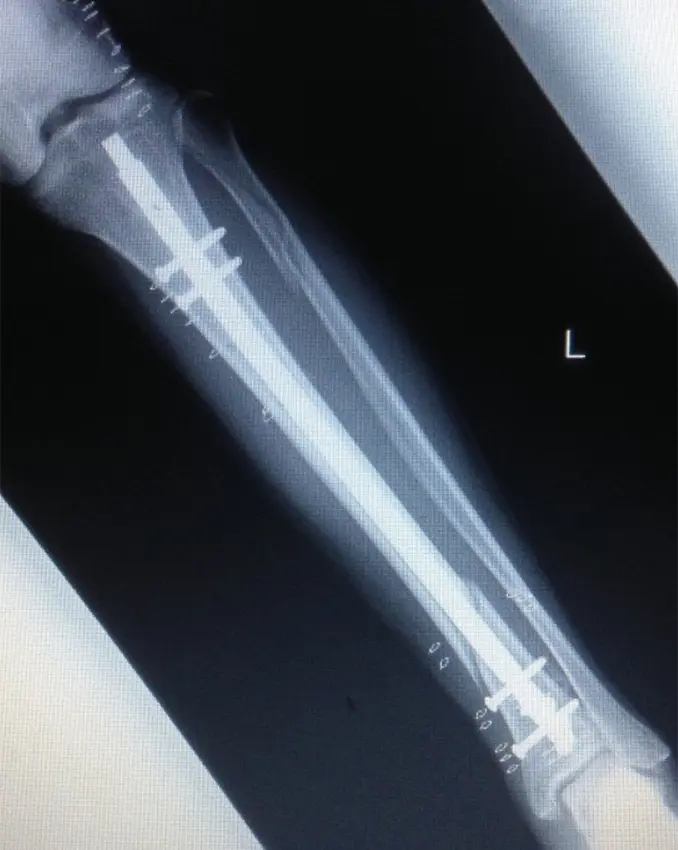

受傷から3日目に創外固定術(手術時間:60分)を施行した。

イメージ下に、脛骨の骨折部を確認、マーキングし、近位骨片に前内側からシャンツスクリューを2本刺入、踵に外側から、第1中足骨骨幹部に足背側からシャンツスクリューを1本ずつ刺入した。シャンツスクリューにクリップオンクランプを繋ぎ、ロッド同士を三角の構造になるようにコンビネーションクランプとロッドで連結し仮固定。イメージ下にて遠位骨片が後方に転位していたため整復し、骨折部の短縮、回旋を除いた所で、クランプを締め直して手術終了とした。

(図2)創外固定後単純X線